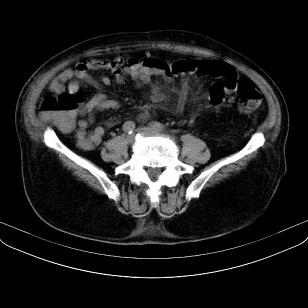

标题: CT21671:男,88岁,左上腹包块 [打印本页]

标题: CT21671:男,88岁,左上腹包块

患者因咳嗽而住院,自觉右上腹包块,无其他不适。

支持;后腹膜脂肪肉瘤诊断。

另肠腔扩张及液平,肠梗阻?